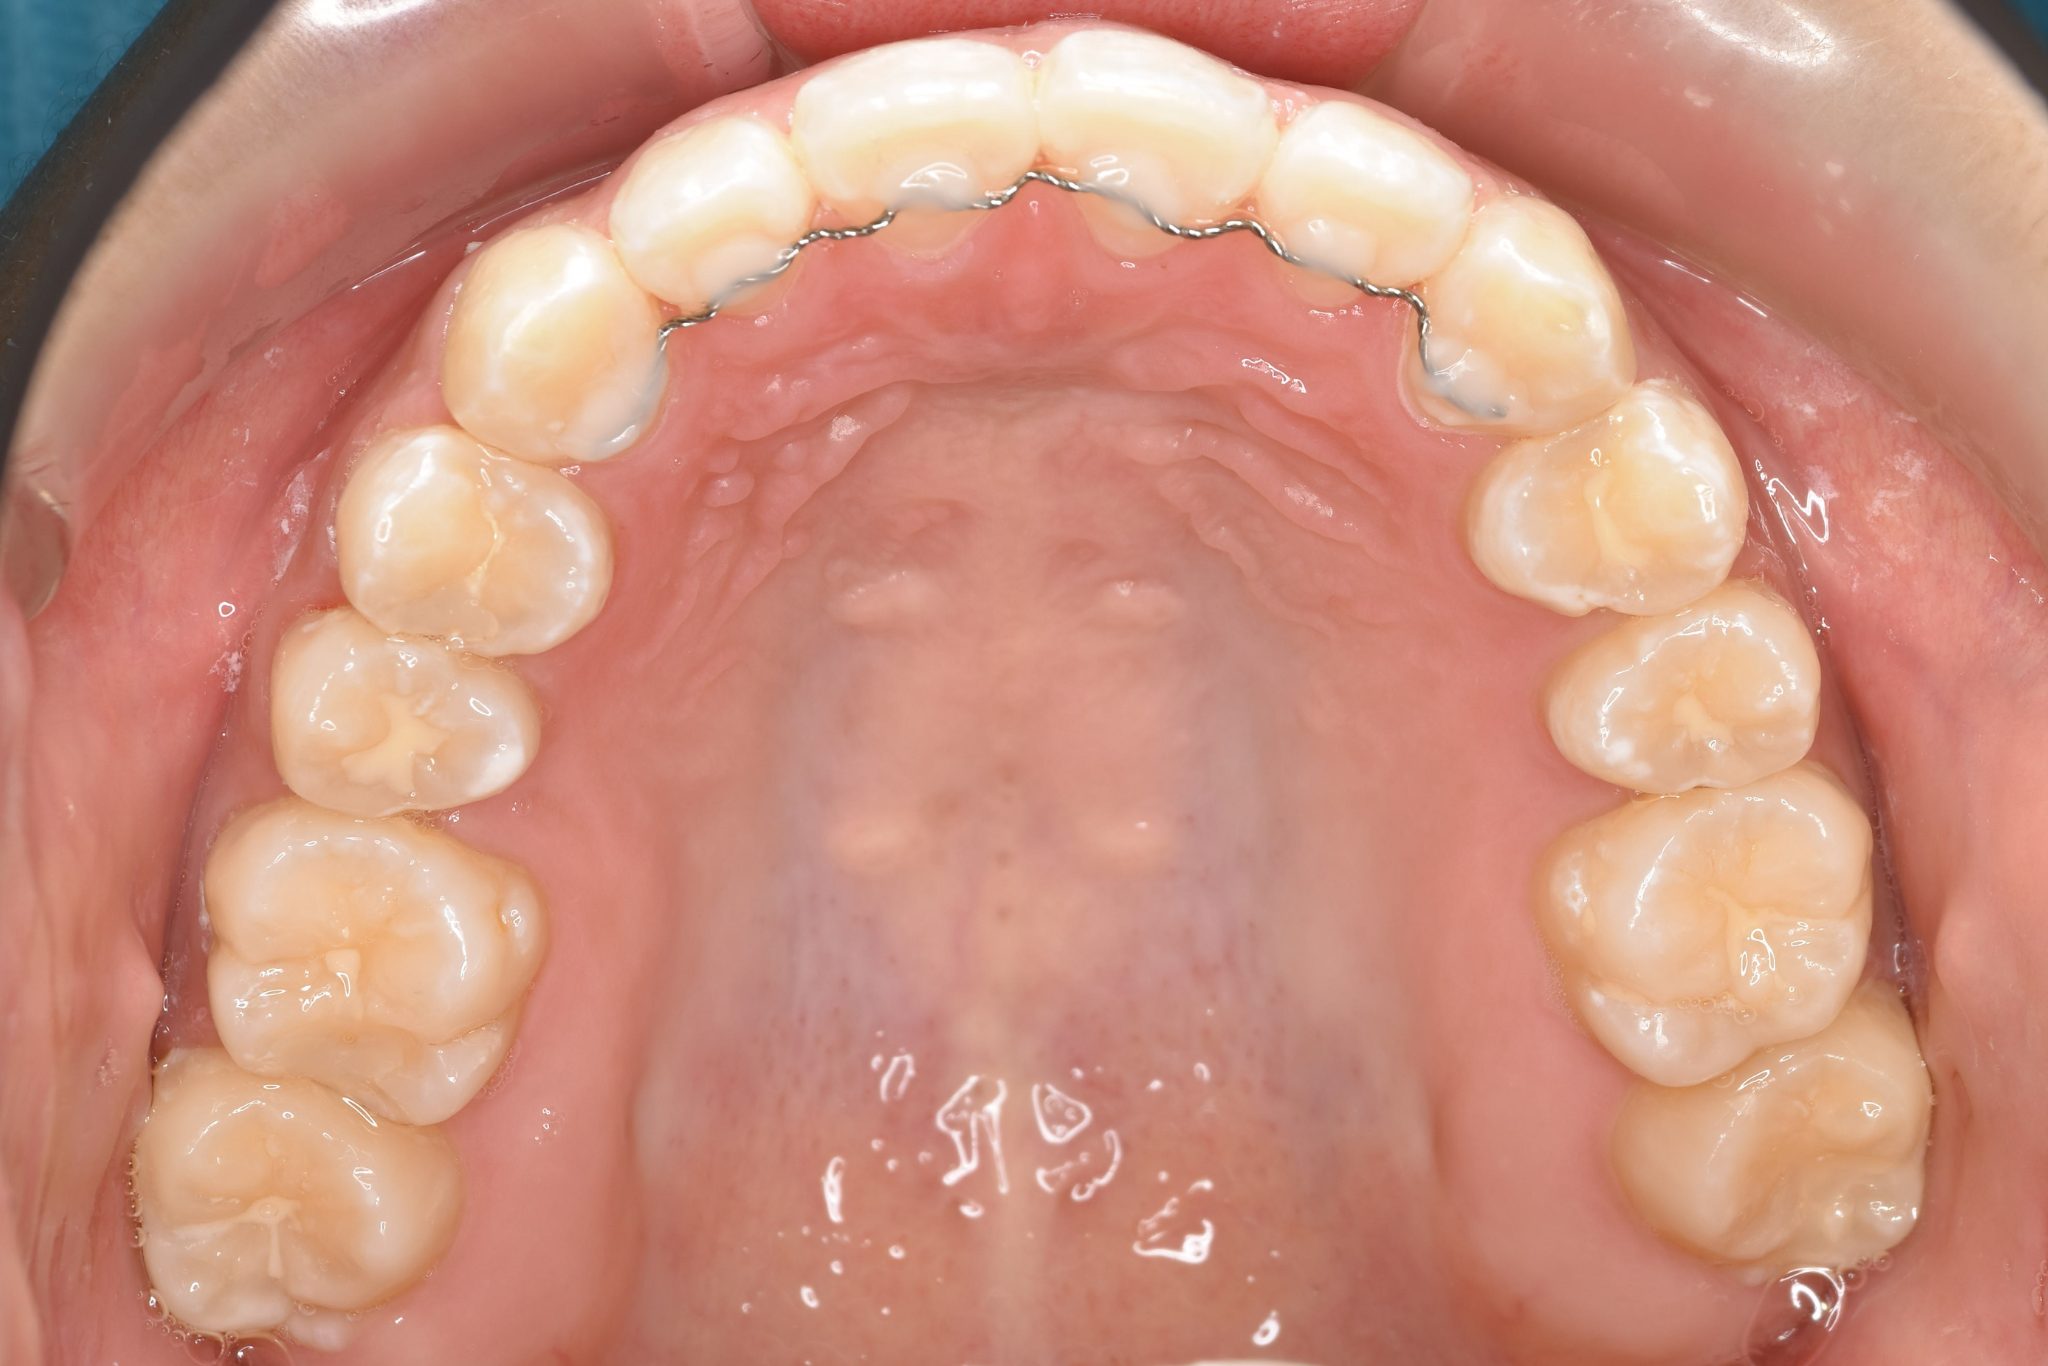

ビフォー

アフター

主訴 前歯の歯並び

施術内容 成人矯正1期治療

治癒期間 1年2か月間

費用 954,800円(税込)